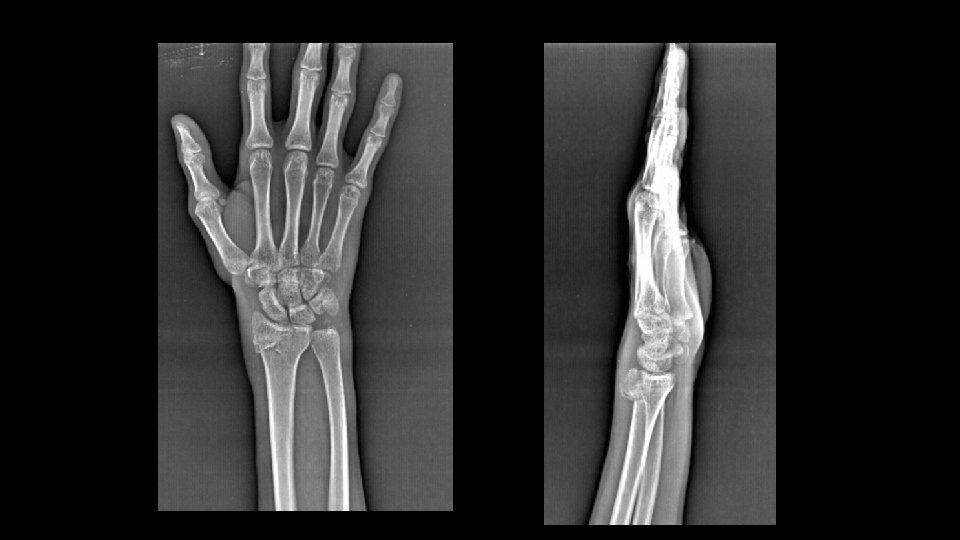

FX RADIOCUBITAL DISTAL FRACTURA DE BARTON • Dorsiflexion y pronación del antebrazo con muñeca estática (accidentes de moto). • Fx intraarticular del radio distal. • Fx del reborde dorsal del extremo distal del radio que se dirige oblicuamente hasta el borde radiocarpiano. • El fragmento radial se desplaza dorsalmente y se acompaña de desplazamiento dorsal del carpo.

FX RADIOCUBITAL DISTAL FRACTURA INVERSA DE BARTON • Es > frec que la de Barton • Cuando la fx afecta el reborde volar de radio distal, con extensión intraarticular y desplazamiento volar del carpo. • Subluxación del carpo.

FRACTURA HUNCHINSON • Del conductor • Fractura intra articular de la base del estiloides radial que se extiende desde el margen radial hasta la ARC. • Impactacion del escafoides contra el estiloides radial o por avulsión del LLR o de los LRC. FX RADIOCUBITAL DISTAL